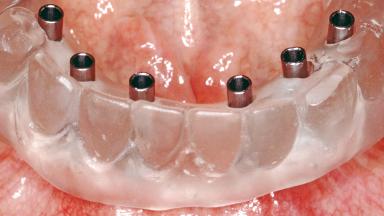

Conventional Loading of Six Implants in the Mandible and Final Restoration with a Full-Arch Metal-Ceramic FDP

A 68-year-old, completely edentulous male patient presented for evaluation and treatment options. He reported excellent general health and was taking no regular medication. He had been edentulous for approximately 12 years, having lost his teeth to periodontal disease and dental caries. The patient’s chief complaint was incompetent function. His secondary concerns included his appearance and the desire for a predictable outcome. He attributed his reduced functional capacity to his lower complete denture, which he described as poor. He was particularly concerned with the denture’s instability and poor fit. In general terms, he was satisfied with the maxillary complete prosthesis. The maxillary prosthesis was characterized by adequate retention, stability, and support, although the fit was considered less than ideal.

# of Implants 6

Type of Implants One-Piece

Retention Screw-retained, with 4 or more splinted implants Screw-retained, with 4 or more splinted implants